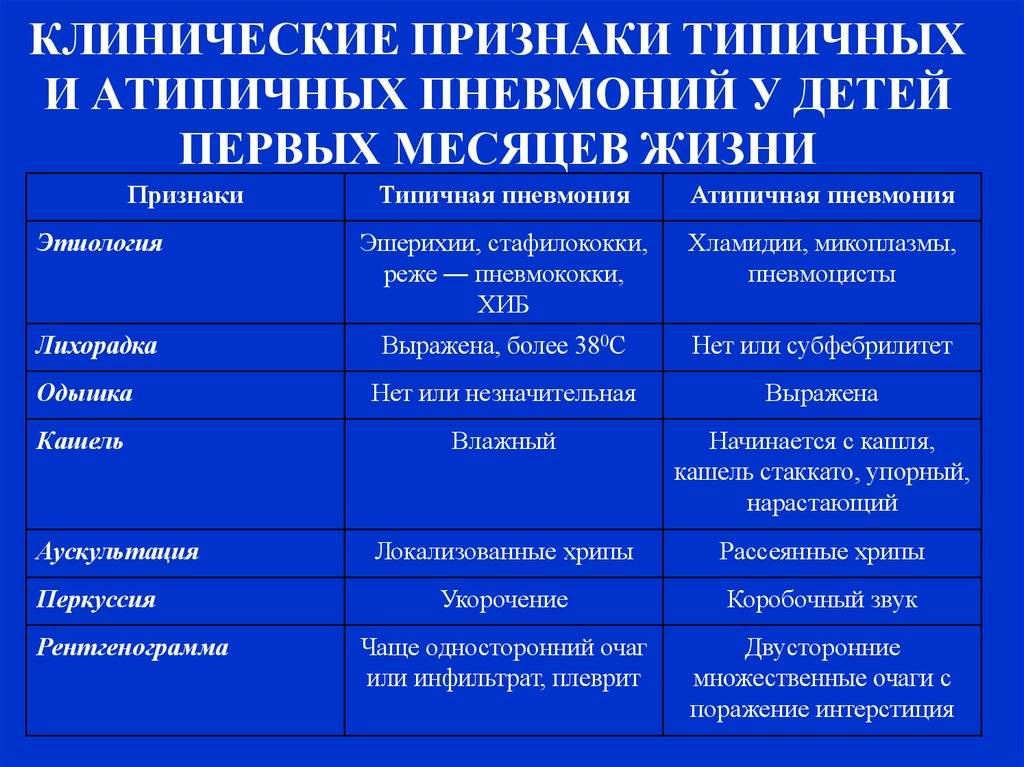

Проявления заболевания во многом зависят от возбудителя и объема поражения легочной ткани. Однако практически для всех видов пневмонии характерны общие симптомы: слабость и утомляемость, головная боль, озноб, резкий подъем температуры (при острой форме заболевания), кашель (в первые дни — сухой, затем становится влажным с обильным выделением мокроты с примесью крови), боль в грудной клетке (на стороне поврежденного легкого), одышка (чем больше очаг воспаления, тем она сильней), посинение кожных покровов.

Пневмония может протекать в острой, подострой (затяжной) или хронической формах, в тяжелых случаях не исключен смертельный исход. Смешанная вирусно-бактериальная инфекция отягощает течение болезни. В зависимости от вовлеченности легких в воспалительных процесс выделяют одностороннюю (когда поражено одно легкое) и двухстороннюю (оба легких) пневмонию.

Пневмонию могут вызывать различные микроорганизмы: преимущественно бактерии (пневмококки, гемофильная палочка, стафилококки, стрептококки и др.), вирусы (гриппа, респираторно-синцитиальный вирус, риновирусы, аденовирусы и др.), редко грибки и паразиты (аскариды, стронгилоиды и др.).

В последнее время отмечается тенденция к увеличению количества атипичных пневмоний, причиной которых становятся нехарактерные (атипичные) возбудители: например, вирусы и внутриклеточные бактерии легионеллы, микоплазмы, хламидии.